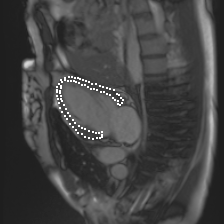

Accurate segmentation and motion estimation of myocardium have always been important in clinic field, which essentially contribute to the downstream diagnosis. However, existing methods cannot always guarantee the shape integrity for myocardium segmentation. In addition, motion estimation requires point correspondence on the myocardium region across different frames. In this paper, we propose a novel end-to-end deep statistic shape model to focus on myocardium segmentation with both shape integrity and boundary correspondence preserving. Specifically, myocardium shapes are represented by a fixed number of points, whose variations are extracted by Principal Component Analysis (PCA). Deep neural network is used to predict the transformation parameters (both affine and deformation), which are then used to warp the mean point cloud to the image domain. Furthermore, a differentiable rendering layer is introduced to incorporate mask supervision into the framework to learn more accurate point clouds. In this way, the proposed method is able to consistently produce anatomically reasonable segmentation mask without post processing. Additionally, the predicted point cloud guarantees boundary correspondence for sequential images, which contributes to the downstream tasks, such as the motion estimation of myocardium. We conduct several experiments to demonstrate the effectiveness of the proposed method on several benchmark datasets.